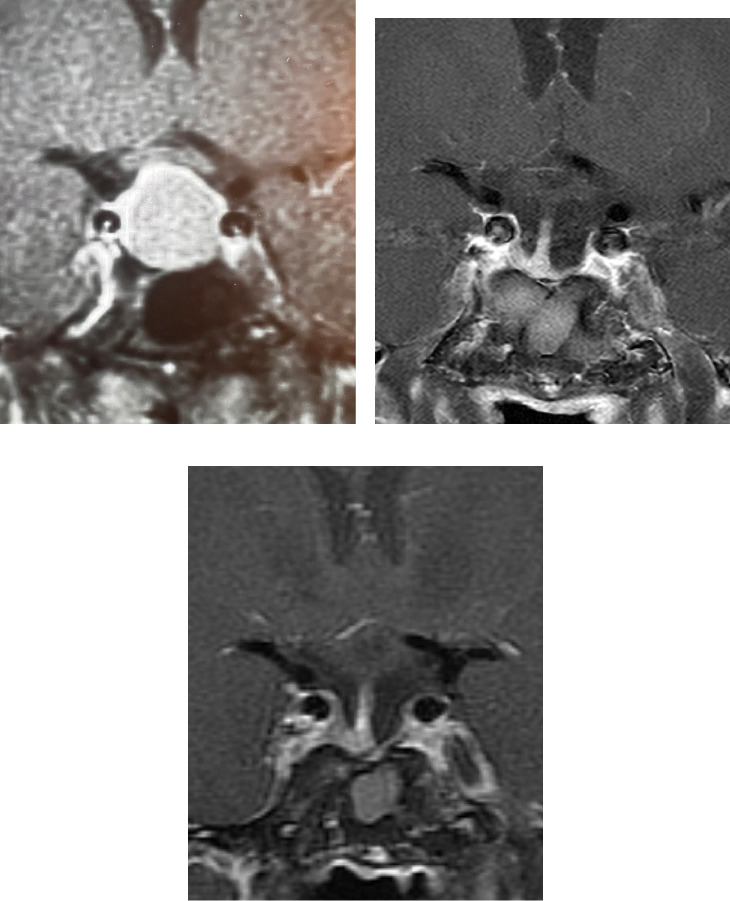

Acromegaly is a rare disease that is caused by a growth hormone (GH) secreting pituitary tumor. This is a case of a 62-year-old man who presented with hypertrophic cardiomyopathy more than 25 years after surgical remission without other known etiologies of left ventricular hypertrophy. The patient initially presented at age 28 with symptoms of acromegaly and diagnosed himself, while several physicians dismissed the diagnosis. He underwent transsphenoidal surgery associated with long-term remission. At age 53, he developed palpitations, light headedness, dizziness, and chest tightness, and an echocardiogram demonstrated left ventricular hypertrophy. At age 60, cardiac magnetic resonance imaging (MRI) suggested hypertrophic cardiomyopathy, which continues to be followed. This case raises the question of whether cardiac morphological changes occur in patients with acromegaly who have GH and insulin-like growth factor-1 (IGF-1) levels well controlled. Cardiac MRI is the most accurate imaging modality for assessment of cardiomyopathy. However, more research is needed to inform clinical guidelines on screening for cardiac functional and morphological changes in patients with acromegaly.

Abstract Image